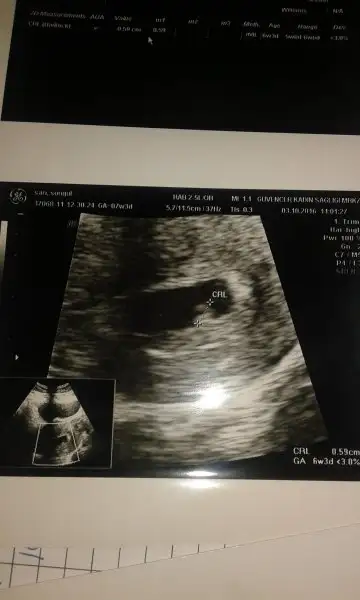

Benimde kizimda senin kiz gibiydi oglumdada simdiki ultrasyon resmin gibiydi. Sanirim bebosin oglan canim :)Eki Görüntüle 1895776 bu kızım 7 yıl önceki ultrason görüntüsü. Eki Görüntüle 1895777 buda şimdi ki

Senin oglum keseye göre tutmus buda kiz bence cünkü teori sende tutuyo :)Karından usg.ilk foto 6+3 ikinci foto 7 haftalık.